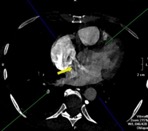

В статье представлен случай успешного хирургического лечения тромбоэмболии легочной артерии у пациентки с высоким риском ранней сердечной смерти на фоне парадоксальной эмболии, осложненной острым нарушением мозгового кровообращения. Криптогенное острое нарушение мозгового кровообращения в комбинации с тяжелой прогрессирующей правожелудочковой недостаточностью на фоне ТЭЛА обусловливает серьезные трудности при принятии решения в отношении тактики лечения у данных больных. Внутрисердечная локализация тромбоэмбола, угрожаемая развитием не только рецидива тромбоэмболии легочной артерии, но и парадоксальной эмболии требует незамедлительного выполнения комплекса дифференциально-диагностического обследования, направленного на верификацию патофизиологического механизма развития заболевания, что во многом определяет эффективность проводимого лечения. Анализ доступных литературных данных, приведенный в работе, а также анализ клинического случая позволяют выработать тактический алгоритм в этой группе пациентов и определить показания к открытому оперативному вмешательству.